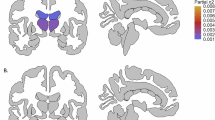

Recent research suggests that brain anatomy may help identify the most effective pharmacological treatment for each individual with bipolar disorder and reduce trial-and-error prescribing. We aimed to investigate whether brain anatomy predicts whether a medication is currently prescribed or has been discontinued, as a proxy for treatment effectiveness. The rationale is that medications that provide clinical benefit without unacceptable side effects are likely to be continued, whereas those with limited benefit or poor tolerability are typically discontinued. We used T1-weighted MRI from twelve ENIGMA-BD cohorts (n = 2462; 473 individuals with BD [61% female, age 18–73] and 1989 controls) to derive regional cortical thickness and surface area and subcortical volumes. Site differences were harmonized using ComBat models fitted on controls’ data. Within cross-validation, models were trained to first adjust for cumulative dose and other covariates and then predict medication status. On test sets, current prescription (vs. discontinuation) of lithium was predicted by greater cortical thickness and reduced surface area, whereas current prescription (vs. discontinuation) of antidepressants and atypical antipsychotics was predicted by greater cortical thickness. Predictive regions for atypical antipsychotics were generally consistent across subgroups of age, gender, illness duration, and history of psychosis, and in the largest site, and differed from those associated with cumulative effects of medication on the cortex. Predictions were poor for subcortical volumes and for antiepileptic mood stabilizers and typical antipsychotics. These findings provide preliminary support that cortical anatomy may help inform future development of biomarkers for treatment selection, pending validation in longitudinal studies.